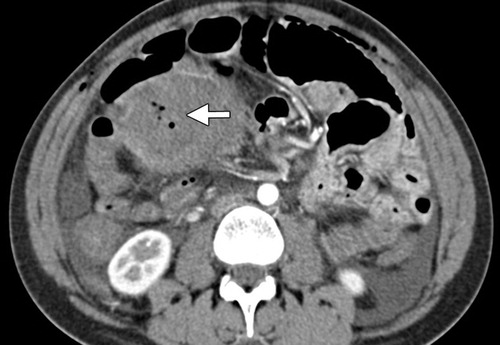

Figure 4: Axial contrast-enhanced CT image shows intrauterine gas bubbles (arrow), which are a normal postpartum finding in the absence of other symptoms.(Reprinted with permission) [5].